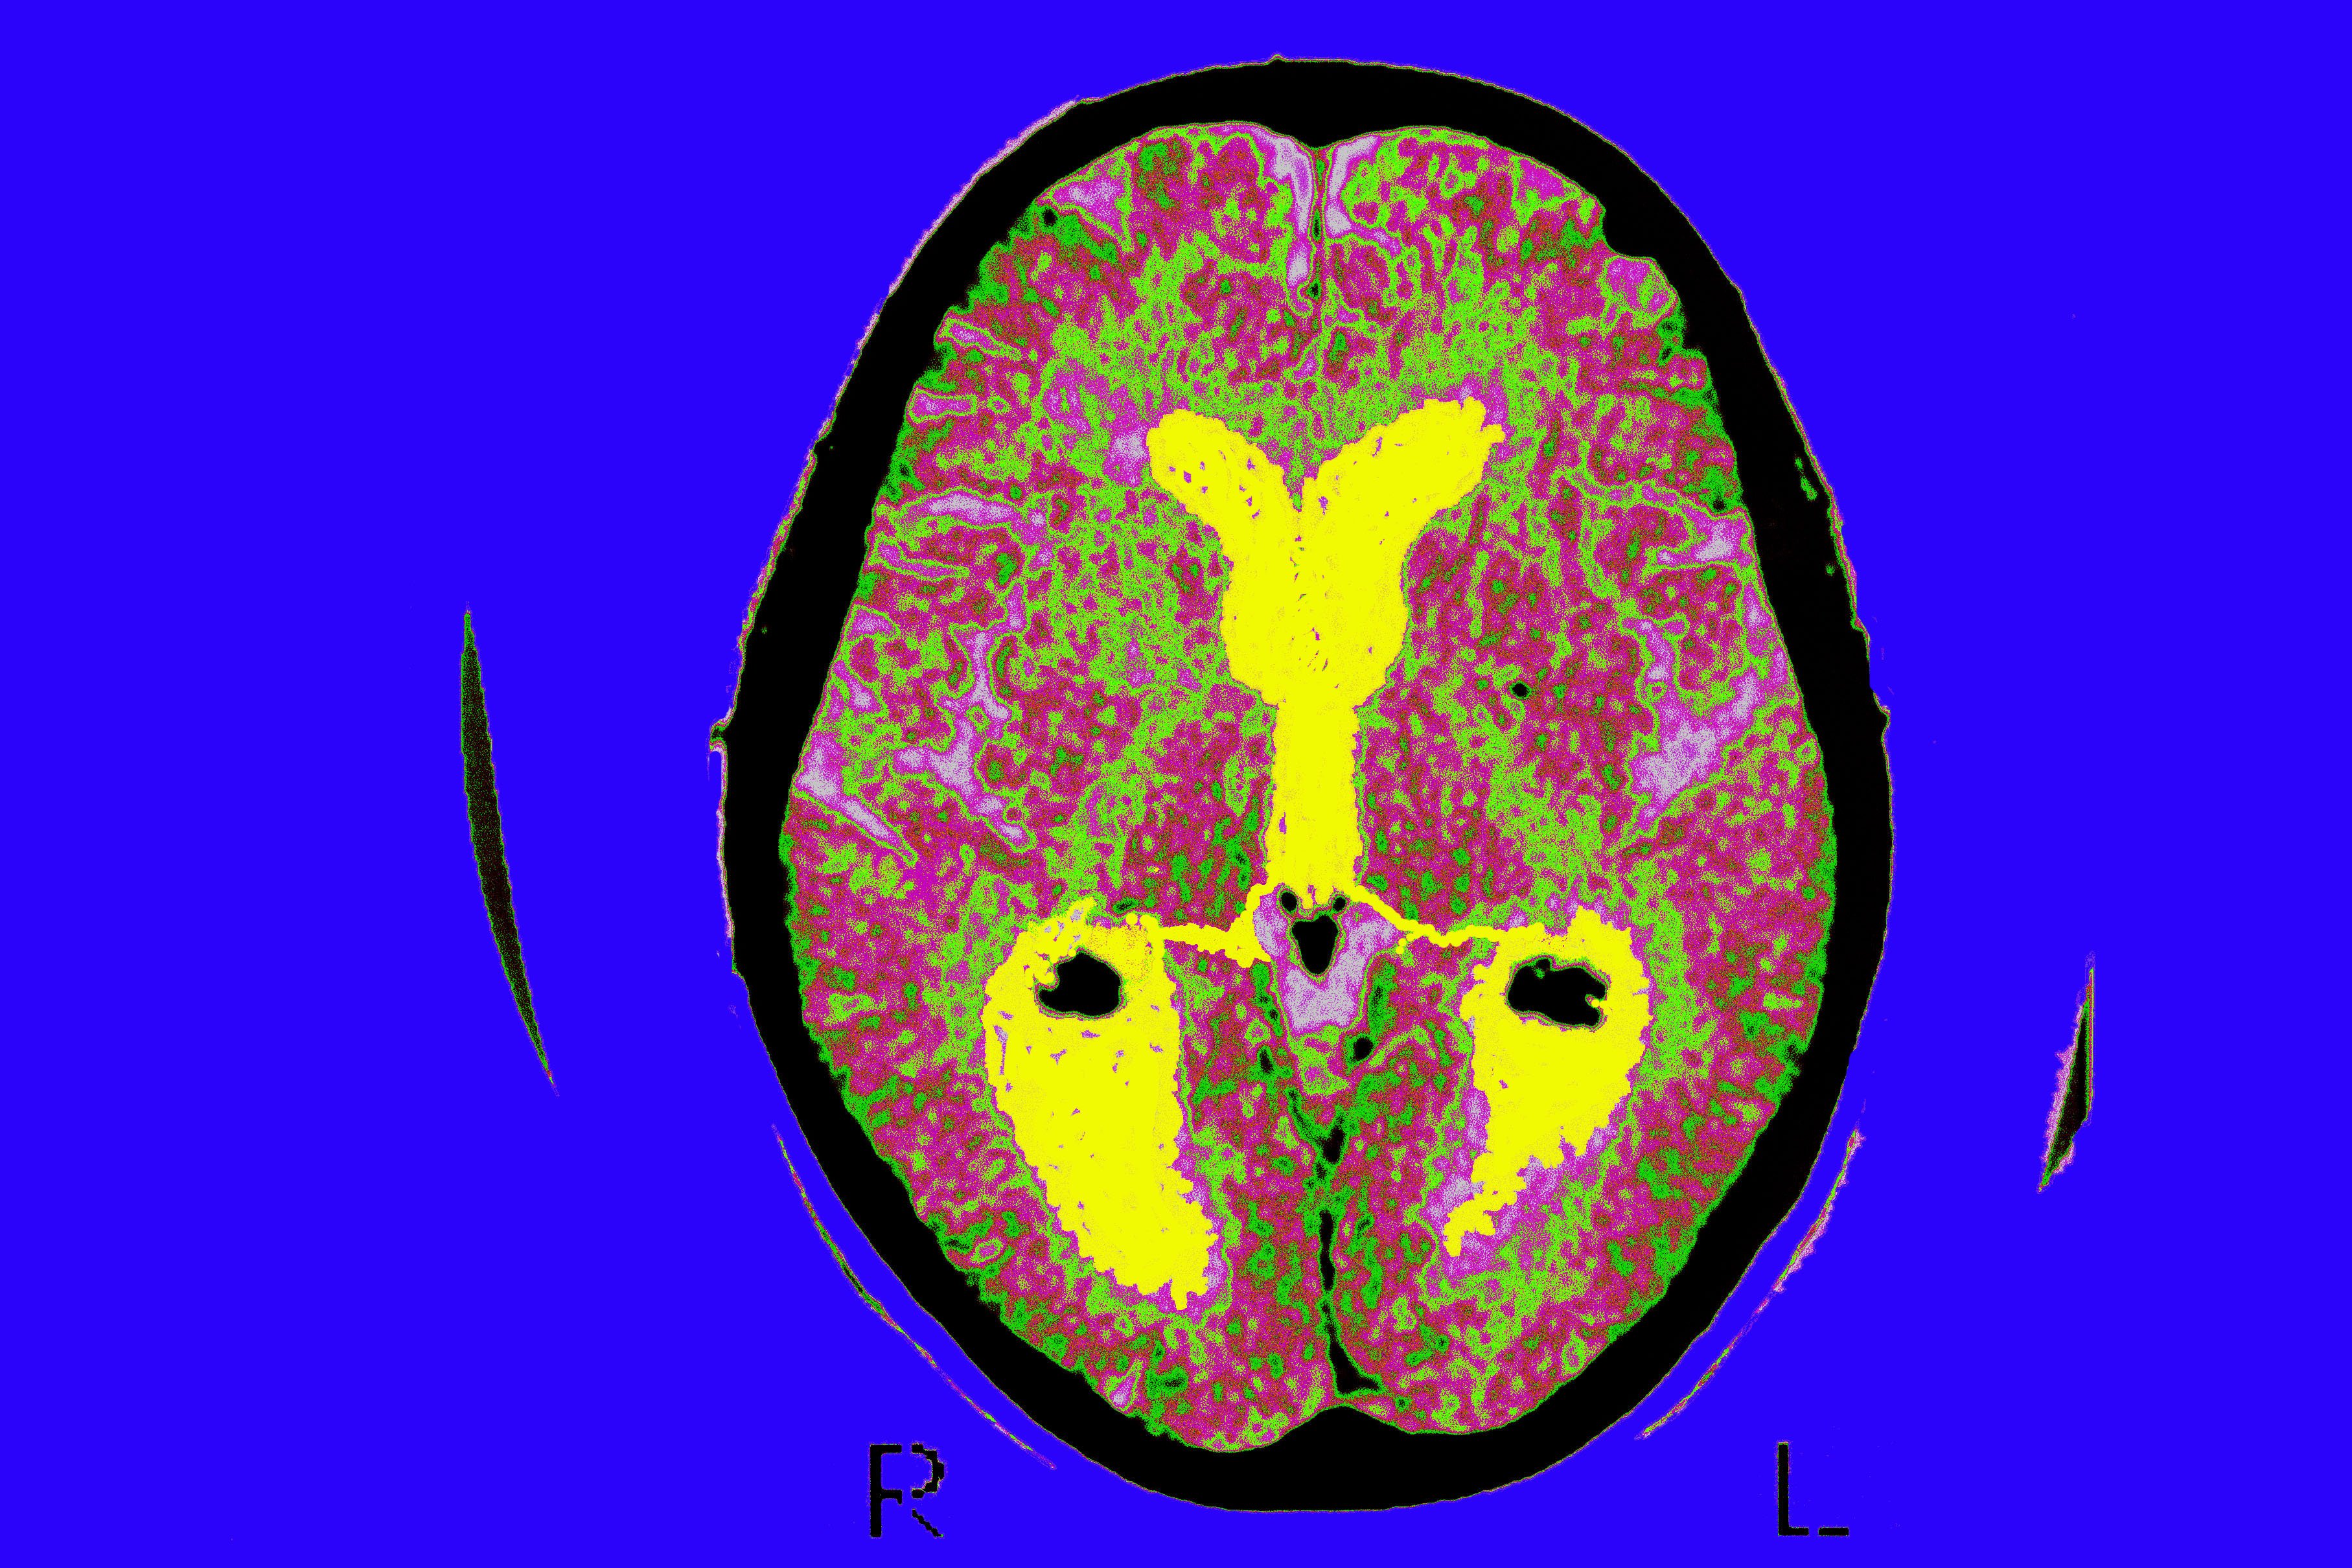

GettyImages-484332326.jpg

Toronto Star reporter Joe Hall's brain scan images taken during his visit to the Toronto Western Hospital's MRI room on July 29, 2015. (Brian B. Bettencourt/Toronto Star via Getty Images)